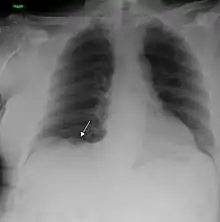

| A chest X-ray showing a tumor in the lung (marked by arrow) | |

Performing a chest radiograph (x-ray) is one of the first investigative steps if a person reports symptoms that may be suggestive of lung cancer. The x-ray may reveal an obvious mass, the widening of the mediastinum (suggestive of spread to lymph nodes there), atelectasis (lung collapse), consolidation (pneumonia), or pleural effusion.[14] Computed tomography (CT) imaging of the chest is often used for diagnosis and may reveal a spiculated mass which is highly suggestive of lung cancer. CT imaging is also used to provide more information about the type and extent of disease. Bronchoscopic or CT-guided biopsy is often used to sample the tumor for histopathology.[15]

Lung cancer can often appear as a solitary pulmonary nodule on a chest radiograph. However, the differential diagnosis is wide and many other diseases can also give this appearance, including metastatic cancer, hamartomas, and infectious granulomas caused by tuberculosis, histoplasmosis, or coccidioidomycosis.[66] Lung cancer can also be an incidental finding, as a solitary pulmonary nodule on a chest radiograph or CT scan done for an unrelated reason.[67] The definitive diagnosis of lung cancer is based on the histological examination of the suspicious tissue in the context of the clinical and radiological features.[1][3]